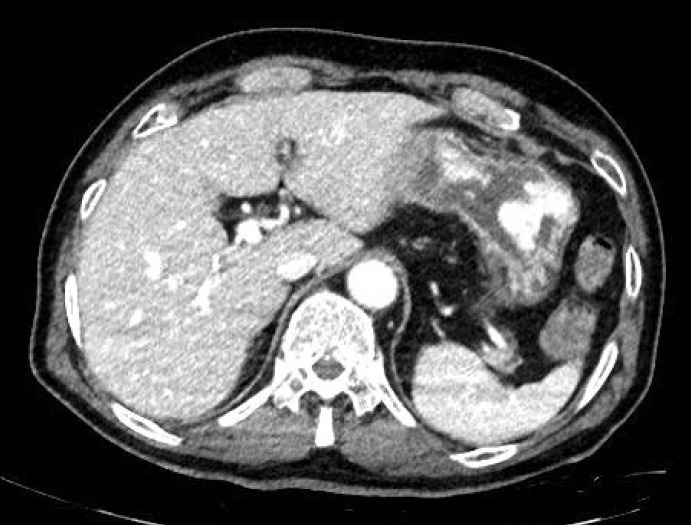

脂肪来源的干细胞因其易于大量获得而备受关注。然而,对其副作用的担忧也被提出。在干细胞治疗过程中,如果医疗器械灭菌不完全和/或细胞加工和培养过程中的卫生不理想,可能会发生分枝杆菌感染。一般来说,分枝杆菌感染最常表现为肺炎;然而,骨骼、淋巴结、皮肤、软组织和血液的感染也会发生。分枝杆菌菌血症的发生相对频繁,但由于干细胞治疗和随后的分枝杆菌菌血症引起胃溃疡的病例尚未报道。在此,我们报告了一位75岁的男性,他在脂肪来源的干细胞注射后出现了分枝杆菌菌血症和胃溃疡。本病例报告提高了人们对脓肿分枝杆菌复合体菌血症和随后的胃溃疡出血的可能性的认识,这是干细胞治疗的一种罕见并发症。

Adipose-derived stem cells are gaining attention because they are easily obtained in large quantities. However, concerns about side effects of their use have also been raised. Mycobacterial infections can develop during stem cell treatment in the event of incomplete medical device sterilization and/or suboptimal hygiene during cell processing and culture. In general, mycobacterial infections most frequently manifest as pneumonia; however, infections of the bones, lymph nodes, skin, soft tissues, and blood also occur. Mycobacterial bacteremia occurs relatively frequently, but cases of gastric ulcers induced as a complication of stem cell treatment and subsequent mycobacterial bacteremia have not been reported. Herein, we report a 75-year-old man who developed mycobacterial bacteremia and gastric ulcers following adipose-derived stem cell injection. This case report raises awareness of the possibility of Mycobacterium abscessus complex bacteremia and subsequent gastric ulcer bleeding-a rare complication of stem cell therapy.